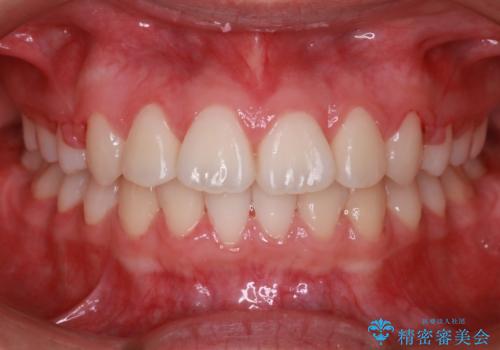

[ 放置し内部で大きく進行した虫歯 ] 神経を守るセラミック治療

担当医 大元洋佑